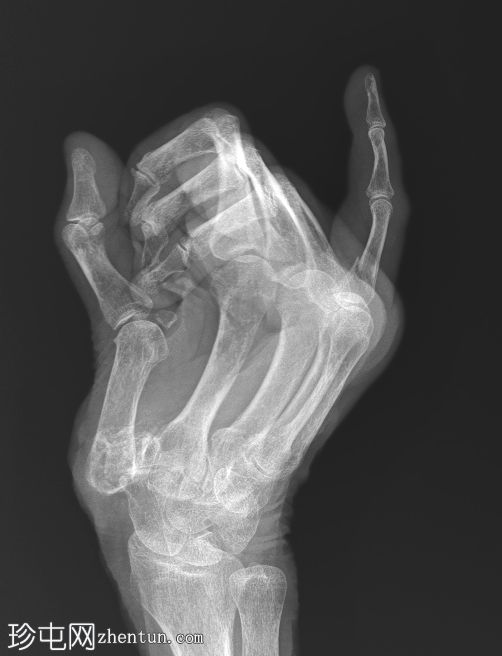

右手X线片

X线片

斜位

小指近节指骨干轻微移位螺旋形骨折,周围软组织肿胀。怀疑拇指掌骨基底部和大多角骨骨折。

第一腕掌关节脱位,周围软组织肿胀。

第二至第五腕掌关节正常。桡腕关节、掌指关节和指间关节正常。尺骨茎突正常。

骨密度降低。